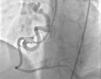

Case reportA 49-year-old woman was admitted to our outpatient clinic with complaints of exertional dyspnea, exertional chest pain, paroxysmal palpitation attacks, and fatigue. She had been treated for diabetes for two years but had no additional risk factors for coronary artery disease. On physical examination, her blood pressure was 130/80 mmHg and heart rate 85 bpm. No pathological sounds were heard during pulmonary and cardiac auscultation. Routine biochemical and hemogram values were within normal ranges. Ejection fraction was 60%, and no serious valve disease was detected on transthoracic echocardiography. Electrocardiography showed sinus rhythm. Right atrial tachycardia was induced with programmed atrial stimulation during a diagnostic electrophysiologic study (Figure 1). Coronary angiography was also performed in order to clarify potential ischemic etiology. While the left coronary and right coronary arteries were found to be normal, a giant fistula was detected from the proximal portion of the right coronary artery to the right atrium (Figure 2). Qp/Qs was 1:1 by oximetry and all right heart pressures were within normal ranges during right heart catheterization. Computed tomography (CT) angiography was also conducted for a detailed anatomical assessment, which showed a fistulized artery about 8 mm in diameter originating from the right coronary artery 2 cm distal to the orifice and draining into the intersection of the inferior vena cava and right atrium after following a tortuous course (Figure 3). The patient's symptoms were considered to be related to a coronary steal phenomenon in addition to the arteriovenous shunt caused by such a large fistula. A percutaneous occlusion procedure was preferred for the patient's comfort and to avoid complications likely to be caused by surgery. During the procedure, a Judkins guiding catheter was placed in the right coronary artery ostium and the fistulized artery was selectively catheterized via microcatheter, then multiple coils with different sizes ranging from 9 mm to 3 mm were sequentially placed in a suitable location in the mid portion of the fistulized artery until total occlusion was achieved (Figure 4). The patient's atrial tachycardia could not be induced again during the control electrophysiologic study repeated at the end of one month. Finally, progressive improvement was observed in exertional capacity, and other symptoms including paroxysmal palpitations completely disappeared during follow-up.

Unless small and asymptomatic, CAFs should be corrected due to the increased risk of thrombosis, endocarditis, rupture, and heart failure. Asymptomatic cases require close follow-up by echocardiography or angiography.6,7 Treatment options include transcatheter occlusion and surgery. Described for the first time by Reidy et al. in 1983, transcatheter occlusion is increasingly used,3 although tortuous and extra-large fistulas with more than one opening and with serious aneurysmal dilatations are not suitable for a transcatheter approach.8 Transcatheter coil implantation is the method of choice in suitable cases. Complications of the transcatheter approach are related to the catheter and guidewire manipulation, as well as coil placement in an unsuitable location or embolization.8 However, the transcatheter approach is superior to surgery in that it increases patient comfort and avoids surgical complications.6 However, in cases unsuitable for a transcatheter approach, surgical treatment is an option, involving median sternotomy and cardiopulmonary bypass.2,8 Risk of post-surgical myocardial infarction is reported as 3%, mortality 2–2.4%, and fistula recurrence 4%.1 With increasing experience and technical advances, transcatheter occlusion has become a successful method. Its reliability and effectiveness are equal to those of surgery, and it is thus preferable in most cases with a hemodynamically important fistula.6,8

In our patient, it was decided to intervene due to the presence of severe symptoms associated with coronary steal and high-output heart failure, and we opted for transcatheter coil embolization after assessing the suitability of the fistulized artery's anatomical features for the procedure. The fistula was successfully occluded by transcatheter coil embolization, with no complications. Although right atrial tachycardia, to which most of the patient's symptoms can be attributed, was induced during an electrophysiologic study, we suspected concomitant coronary artery disease. We therefore performed coronary angiography before deciding on any treatment for atrial tachycardia. After detecting a giant right coronary fistula and excluding coronary artery disease, we hypothesized that the patient's atrial tachycardia might have been caused by this fistula, so we opted to treat it first and treat the atrial tachycardia later. The tachycardia could not be induced again during the control electrophysiologic study repeated after one month; the patient stated that her symptoms, including paroxysmal palpitations, had completely disappeared, and her exertional capacity was also substantially improved during the follow-up period.